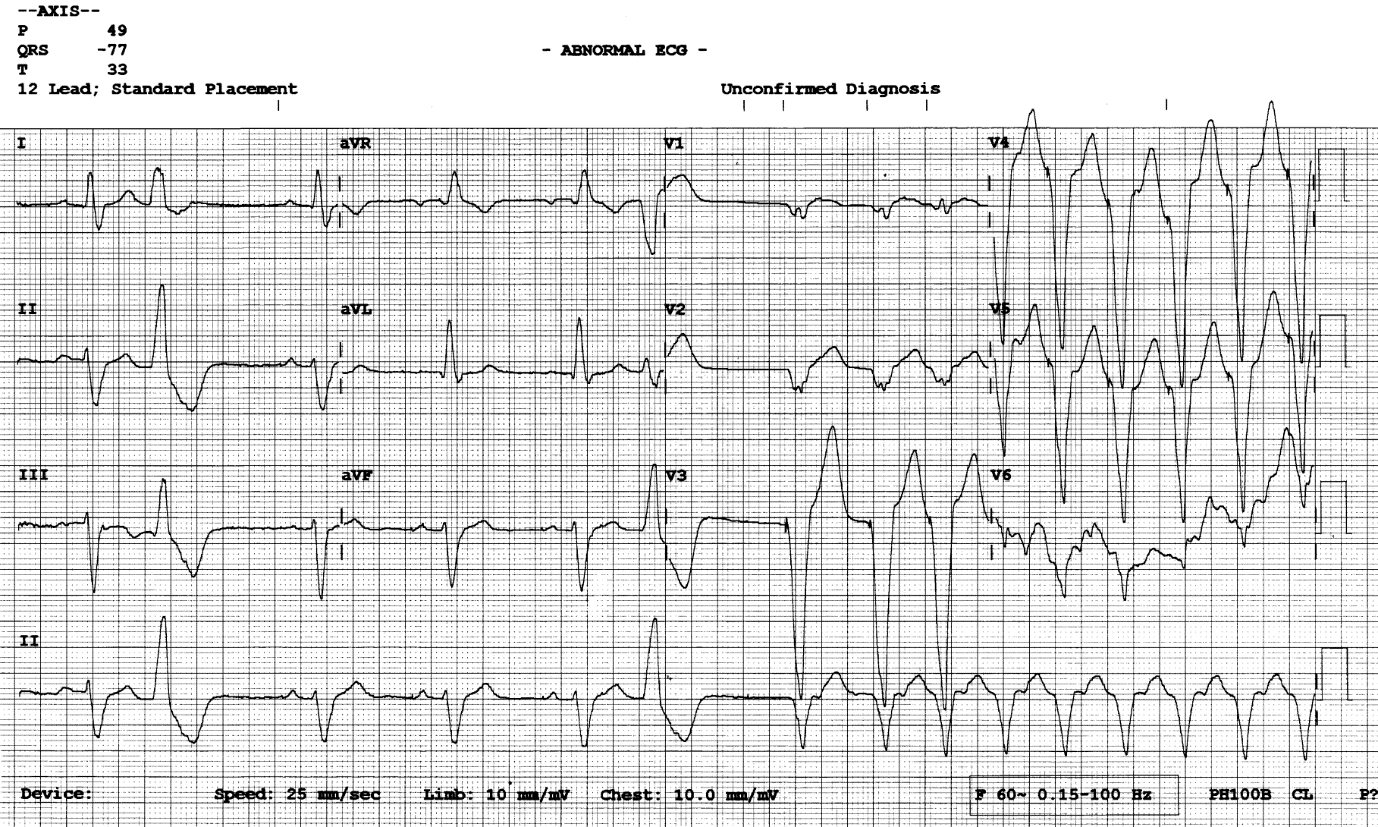

Figure 2

12 lead ECG with annotations. Blue down arrows show subtle atrial pacing artefacts. Blue up arrows show retrograde P waves in the ST segment of the PVC’s. Blue stars show ventricular pacing artefacts. The blue circle shows where an expected AP impulse should have been delivered.

The answer is pacemaker malfunction with the ECG capturing the onset of a pacemaker mediated tachycardia (PMT) triggered by loss of atrial capture. Non-sustained VT and SVT with BBB can be ruled out as broad complex beats have pacing spikes preceding each QRS (blue stars) indicating ventricular pacing. PVC’s set up the circumstance for PMT creating a compensatory pause and bringing in atrial pacing but are not directly responsible for the episodes. The episodes are not associated with physical activity and show sudden onset of paced tachycardia which is not typical for rate responsive pacing behaviour.

ECG Review

The ECG starts with (1) an atrial sensed ventricular sensed event (AS/VS). Note the round shaped sinus P wave and no pacing artefact preceding the P wave or QRS complex. The next event (2) is a PVC which has a subtle retrograde P wave (1st blue up arrow) within the ST segment. This suggests the presence of VA conduction however here the retrograde P wave falls in the post ventricular atrial refractory period (PVARP) and does not affect pacemaker timing intervals. The lower rate interval (60 bpm) times out and the next event (3) is an atrial paced beat which has good AV conduction (AP/VS). There is a subtle atrial pacing artefact (1st blue down arrow) preceding the P wave and a slightly peaked paced P wave morphology which is different to the previous sinus sensed P wave. The next two events (4&5) are AP/VS events at the lower rate interval of 60 bpm. Event (6) is another PVC. After this PVC the lower rate interval times out again, but this time there is no paced or sensed atrial event (blue circle). Event (7) is a ventricular paced (VP) complex with a clear pacing artefact preceding the QRS (1st blue star) which is followed by 8 further ventricular paced beats (8-15) occurring at the upper rate limits of 130 bpm.

The sequence is typical of a pacemaker mediated tachycardia initiated by a loss of AV synchrony which in this case is due to loss of atrial capture. It is a rhythm which requires intact VA conduction and occurs when a ventricular paced event or PVC conducts back to the atria giving rise to a retrograde P wave which falls outside of the programmed PVARP. The retrograde P wave is sensed as an atrial event which triggers an AV interval. When the AV interval times out a ventricular paced beat is delivered and the sequence repeats until there is loss of atrial sensing, loss of retrograde conduction or a PMT prevention algorithm is activated.

In the acute setting a paced broad complex tachycardia at rest at the upper tracking rate most commonly 120/130 bpm should raise suspicion of a PMT. Other differentials include tracking of sinus or atrial tachycardia, inappropriate rate response behaviour, failure to mode switch or inappropriate programming of a device algorithm.